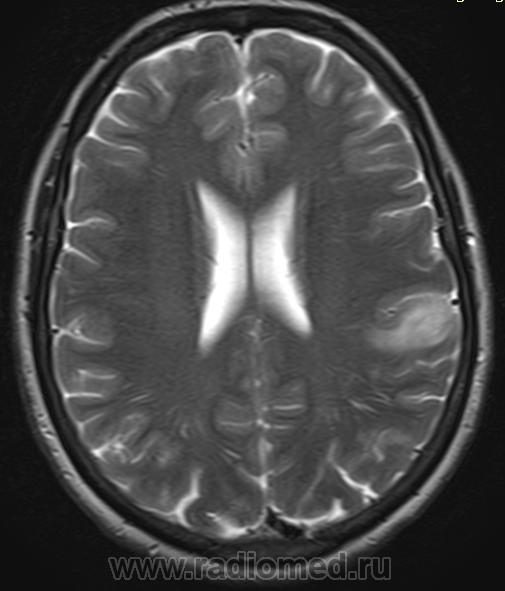

Хроническая ишемия головного мозга и лейкоареоз: симптомы и лечение